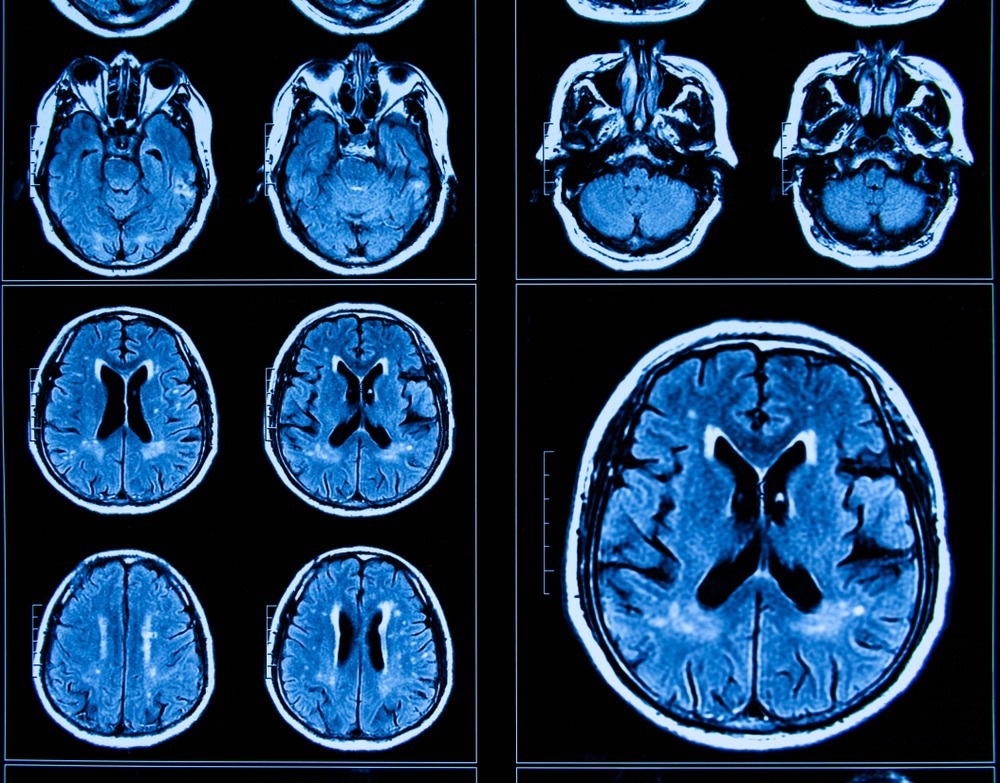

Study: Effects of the COVID-19 Pandemic on Mental Health and Brain Maturation in Adolescents: Implications for Analyzing Longitudinal Data. Image Credit: Shan_shan / Shutterstock.com

In addition to self-reported mental health symptoms, a subset of the study cohort also provided magnetic resonance imaging (MRI) scans of their brains to obtain cortical thickness and subcortical measurements. These values were used to calculate brain age gap estimate (BrainAGE) values for all study participants through the use of a sex-specific machine-learning-based model developed by the ENIGMA-Brain Age working group.

Analysis of the MRI scans demonstrated that peri-COVID group participants had reduced bilateral cortical thickness, as well as greater bilateral hippocampal and amygdala volumes. Furthermore, the peri-COVID group was found to have a greater BrainAGE as compared to those in the pre-COVID group.

These neuroanatomical differences indicate that the brains of adolescents who experienced COVID-19 lockdowns aged at a much more rapid rate as compared to their peers who were assessed before the COVID-19 pandemic. Similarly, larger positive BrainAGE measurements indicated that the brains of the peri-COVID group also appeared older.